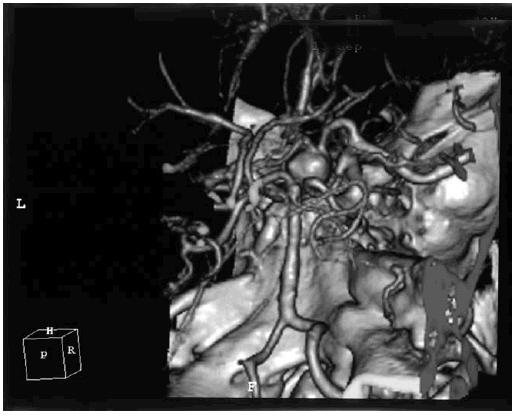

При разрыве аневризмы передней соединительной артерии, сопровождающемся субарахноидальным или паренхиматозным кровоизлиянием и вазоспазмом в системе передних мозговых артерий, развиваются выраженные когнитивные расстройства: нарушение памяти на фоне общих аффективных изменений личности с явлениями расторможенности и нарушением контроля над протеканием психических процессов, нередко с дезориентировкой во времени и пространстве и конфабуляциями [114]. Именно такая клиническая картина наблюдалась у пациента с массивным субарахноидальным кровоизлиянием с разрывом крупной мешотчатой аневризмы передней соединительной артерии, КТ-ангиография которого представлена на рис. 6.2.

Иллюстрация к книге — Деменция. Диагностика и лечение [i_005.jpg]

Рис. 6.2. КТ-ангиография с картиной массивного субарахноидального кровоизлияния у пациента с аневризмой передней соединительной артерии